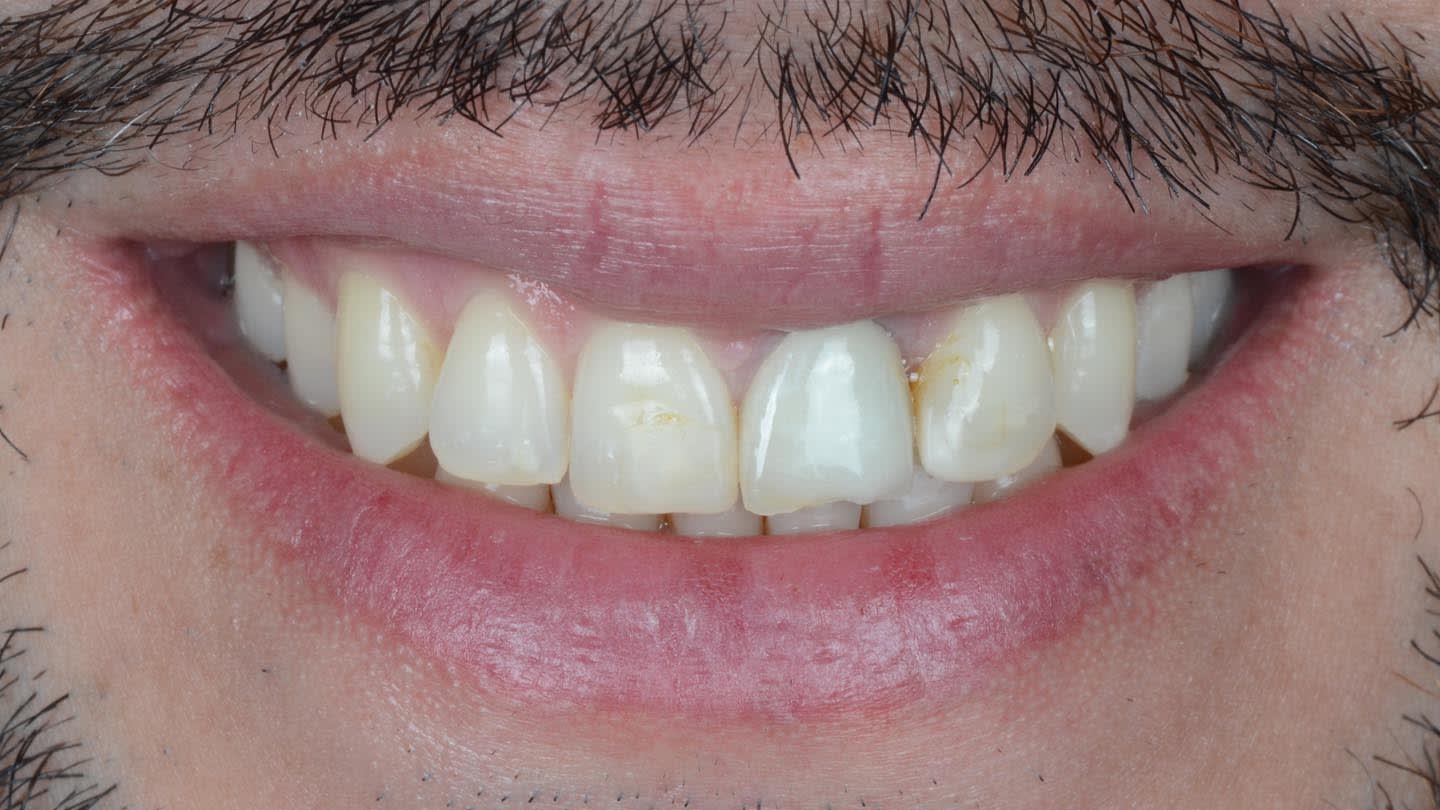

A 40-year-old male patient presented to the author’s (MR) office with the request to improve the esthetics of his smile, as there were several extensive infiltrated composite restorations and a chipped crown showing a severe dark color on an endodontically treated tooth (Figure 1 and Figure 2).

Following a comprehensive clinical, radiographic, and initial photographic assessment, ceramic restorations were chosen to restore function and esthetics. Given that the underlying structure of tooth No. 9 was presented with a fractured crown, a metal cast post, and dark discoloration, it was decided to fabricate a crown with an opaque core using high-opacity LDS ceramic along with a bonded lithium-disilicate veneer on top to enhance the esthetic outcome. For teeth Nos. 7, 8, and 10, LDS ceramic veneers were chosen.